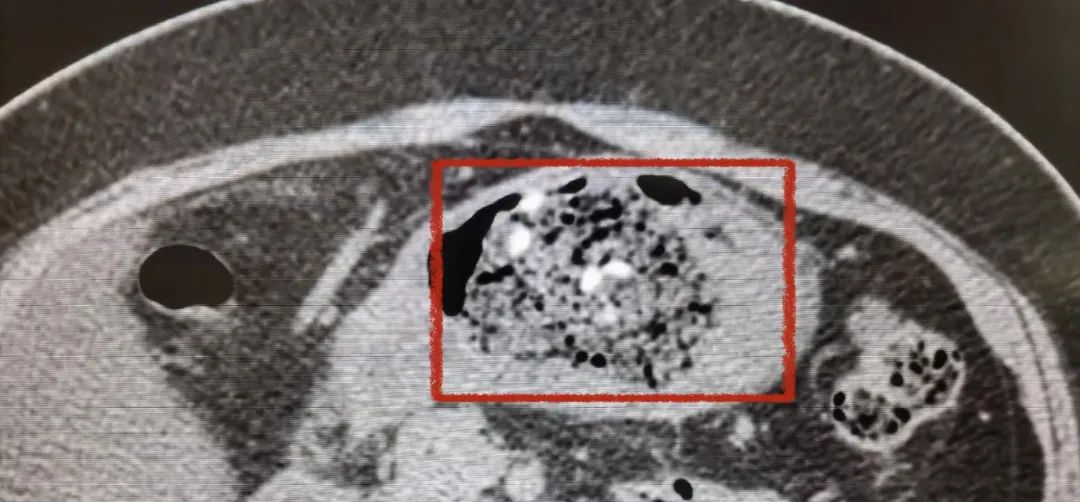

原来张女士喜欢吃山楂,有时候半夜吃几颗,但是最近吃了之后出现了胃痛、腹胀、打嗝等症状,服用促消化药也没有效果。最近,张女士来到南翔医院消化内科就医。腹部CT检查显示,张女士的胃腔内可以看到多个块状内容物,张女士被诊断为“胃结石”。

胃结石的ct显示